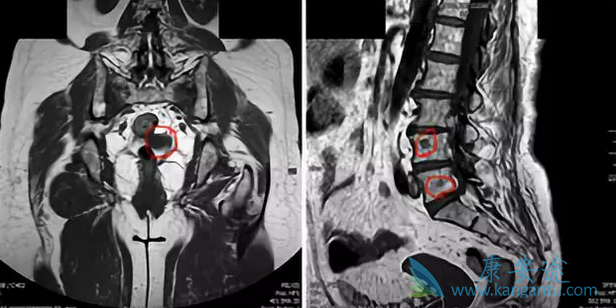

012年7月,一个55岁的女性确诊为左侧局部晚期乳腺癌,激素受体阳性、HER2阴性,先做了8个疗程的新辅助化疗,然后做了彻底的手术、术后的放疗。然后,接受阿那曲唑内分泌治疗——这一系列安排,都是常规的普通治疗。2015年3月,右侧腋窝淋巴结肿瘤复发,穿刺证实是肿瘤转移。于是,开始接受传统方案的化疗:长春瑞滨、顺铂、5-Fu。2015年12月,多发骨转移。下图红圈,显示的就是病灶的部位。由于这些骨转移,患者疼痛明显,依靠止痛药镇痛,晚上依然无法入睡。

癌症传统治疗